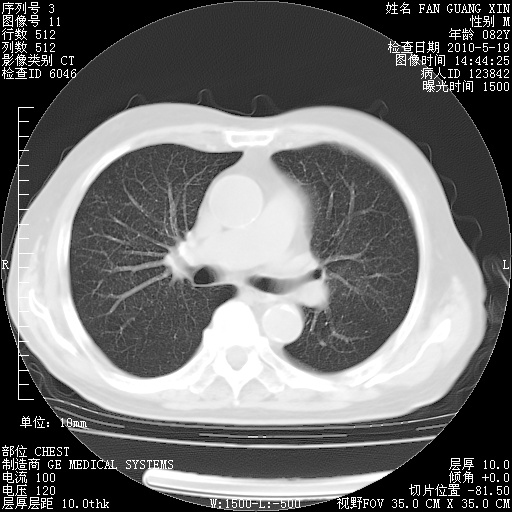

复查肺部CT,明显好转。为什么发热呢?

治疗3周后的肺部CT

治疗3周后的肺部CT纵隔窗